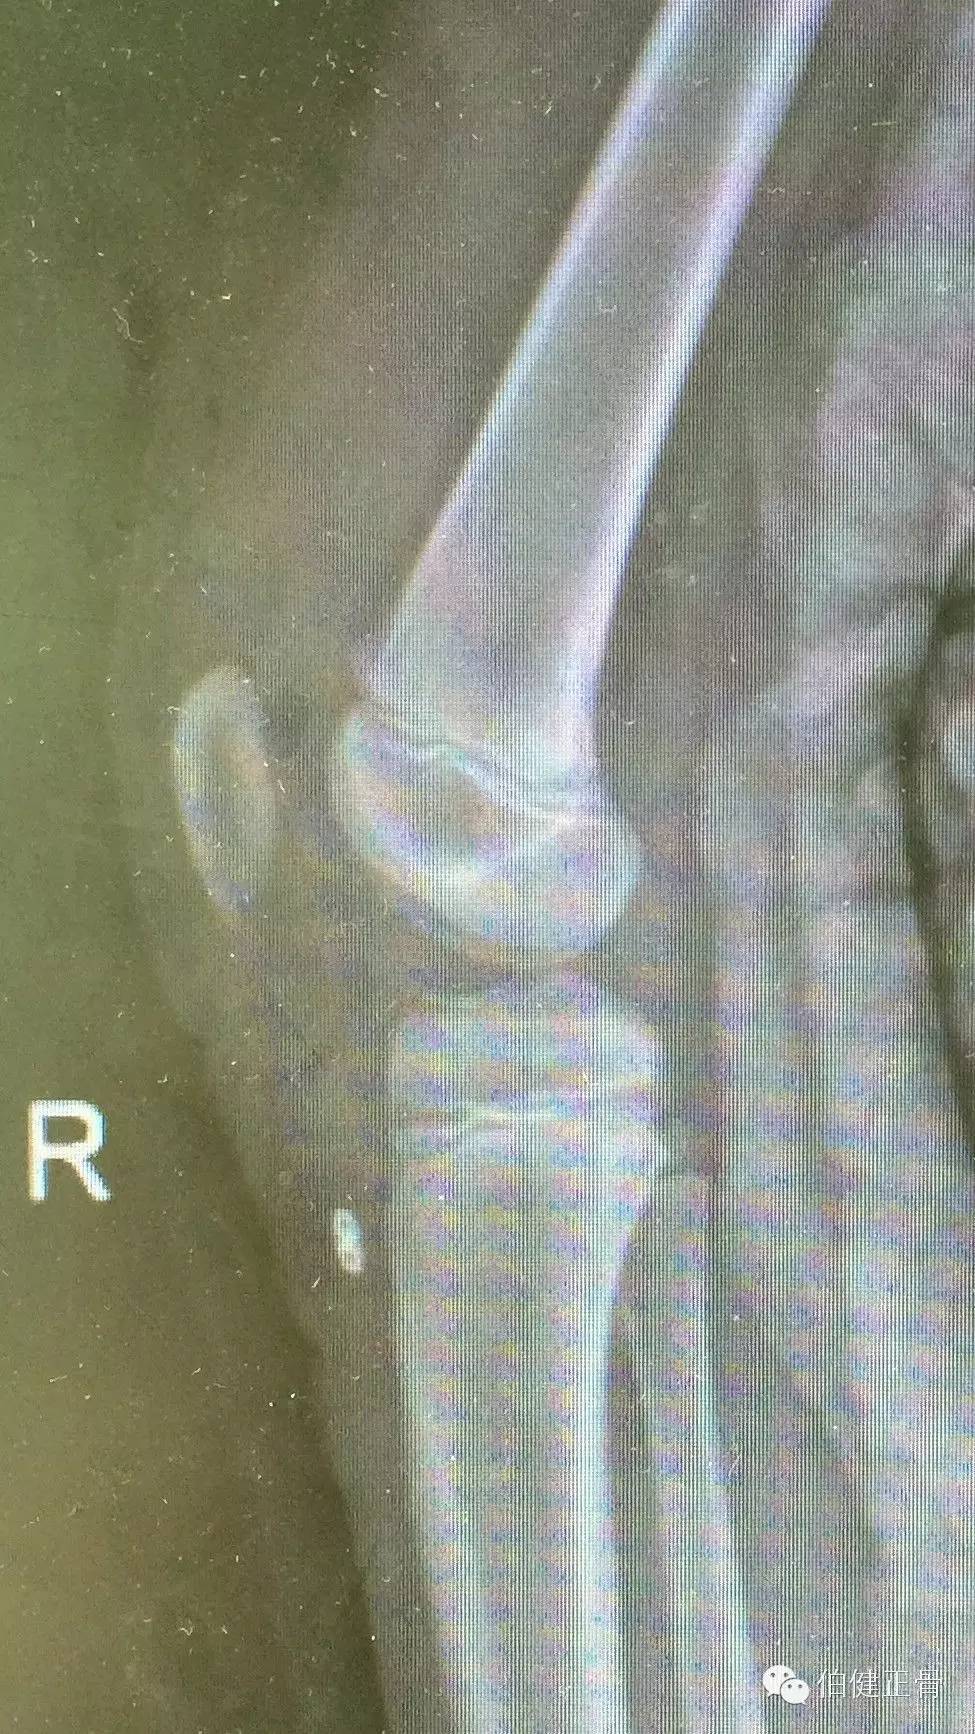

术后复查膝关节正侧位片,骨折解剖复位,完美收工:

侧位可看出我们的战略思路:

纽扣于胫骨之间有少许空位,是因为小儿骨膜厚所致。